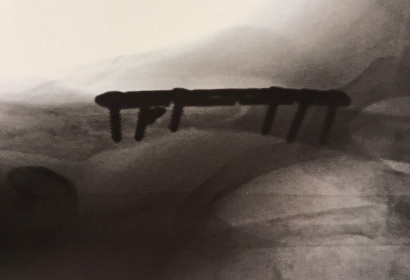

Distal Clavicle Repair with Tensioned Cerclage Repair with Bone Tunnels

Fracture on the left with the repair on the right.